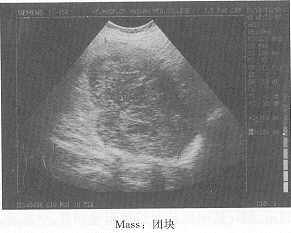

B超显像脾血管肉瘤伴脾静脉瘤栓1例

患者女 ......